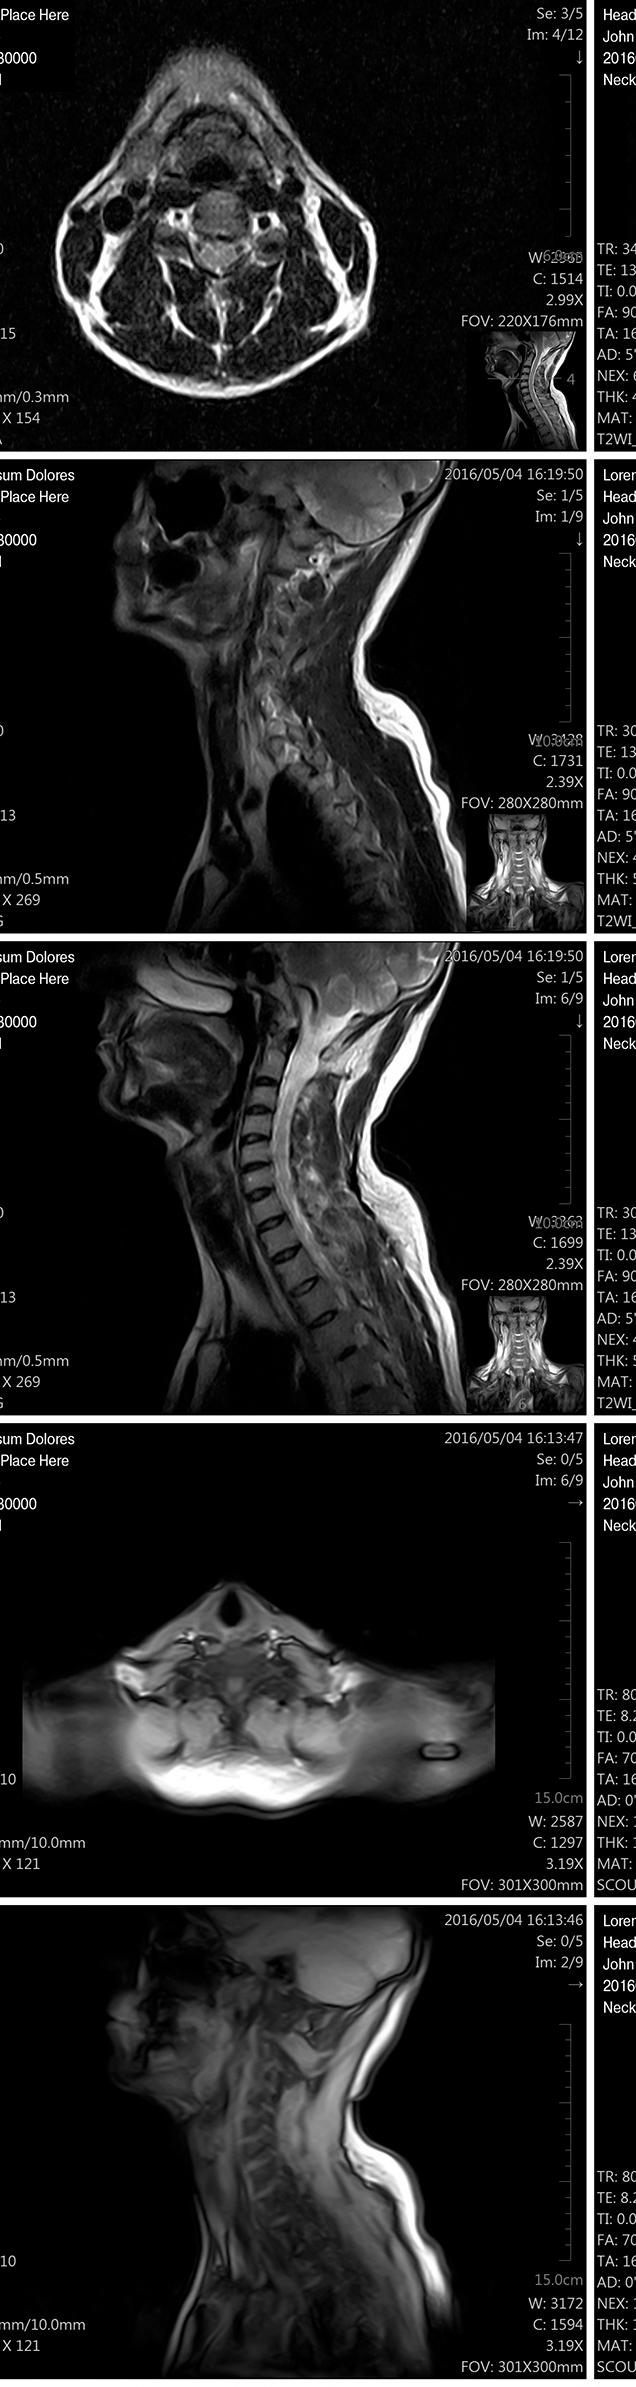

Diffusion tensor imaging (3T, 32 encoding directions, b=800 s/mm, 2mm isotropic resolution) reveals that high levels of soccer heading over two years is associated with changes in brain microstructure similar to findings seen in mild traumatic brain injury. Image from Michael Lipton, MD, PhD, of Columbia University, et al.